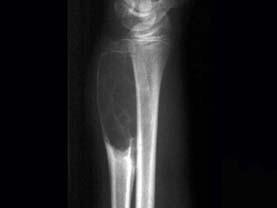

男性,17岁,近2年来感右前臂疼痛,肿胀,2周前由于疼痛加剧,查体右前臂压痛明显,皮肤稍显红肿,请结合所提供图像,选择最佳选项 ( )A、软骨...